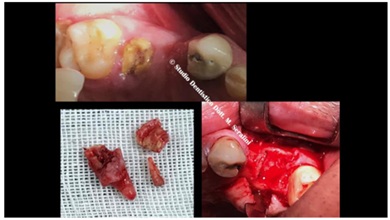

After the avulsion and careful dressing (toilette) of the surgical site, 2 implants were inserted, a standard 3.75 di 13mm and a 2s implant for the crestal Sinus Lift (Yellow arrow in figure 15).

Figure 15: Implant allocated.

An animal bone graft is required together with growth factors shown in figure 16.

Figure 16: Animal Bone graft mixed with P.R.P.

Post-surgical radiographic control, which shows that there is no graft inside the sinus and that the antrum retains the normal diaphanous (Figure 17).

Figure 17: Post Surgery Control, normal diaphanous inside the sinus.